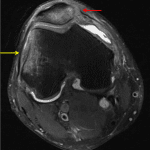

- Cortical irregularity along the medial margin of the patella and along the lateral margin of the lateral femoral condyle

- Large lipohemarthrosis

- Transient patellar dislocation with lipohemarthrosis

Cortical irregularity along the medial margin of the patella and along the lateral margin of the lateral femoral condyle concerning for impaction fractures related to transient lateral patellar dislocation. An avulsion fracture from the medial patella is also a consideration.

Large lipohemarthrosis.